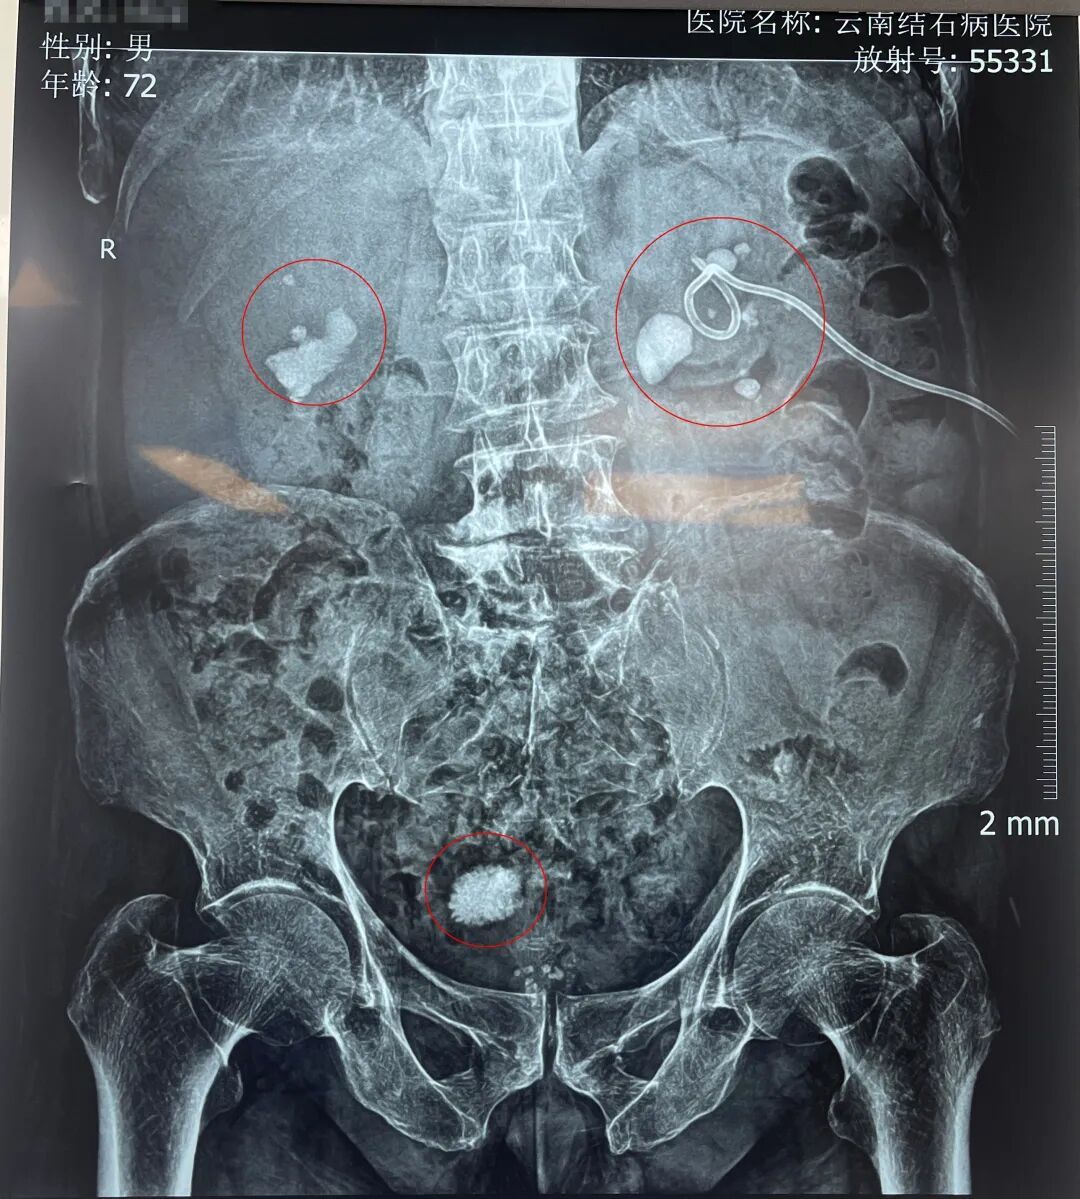

入院后,黄鸿宾主任为周爷爷安排了全面系统的检查。结果显示,其身体状况犹如一座年久失修的老屋,多处功能受损:前列腺增生伴钙化、膀胱结石、双肾多发性结石伴积水、脂肪肝、高血压等。

周爷爷的检查片子